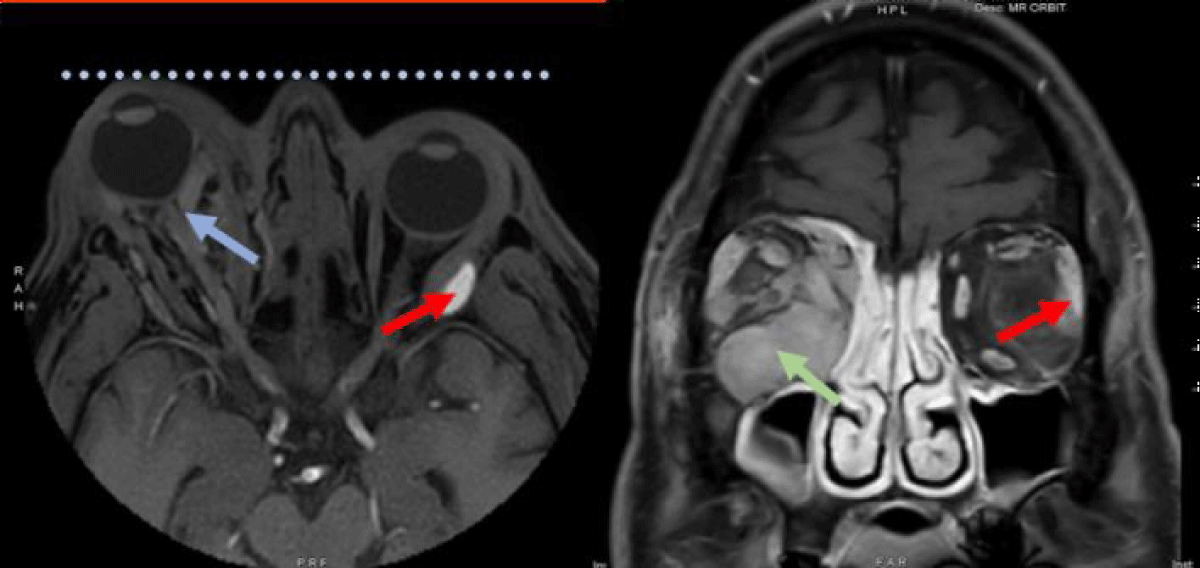

MRI of the orbits demonstrated progression of his right orbital mass with increased proptosis, a stretched appearance of the optic nerve, and tethering of the posterior globe with a stable left orbital mass (Figure 2). This acute swelling of the right orbital mass was deemed to be likely related to an inflammatory reaction to his first radiation treatment. Intravenous dexamethasone at a dose of four milligrams was administered with significant improvement in ocular symptoms. He was discharged with a 9-day oral dexamethasone taper along with dorzolamide/timolol eye drops, brimonidine eye drops and Lacri-Lube ointment.

Figure 2: Axial (left) and coronal (right) T1 MRI images with contrast demonstrating greater right eye proptosis (dotted line) with a stretched appearance of the optic nerve and tethering of the posterior globe (blue arrow). Increased swelling due to acute inflammatory reaction in the right orbital mass (green arrow). The left orbital mass remains stable (red arrow).